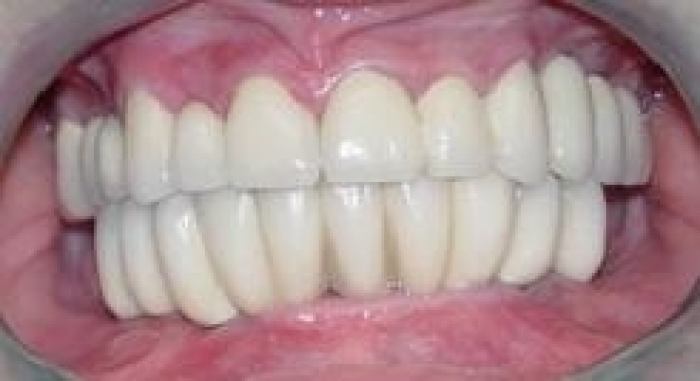

Sorriso final, do caso terminado em Junho de 2006

Imagem Final Intra Oral